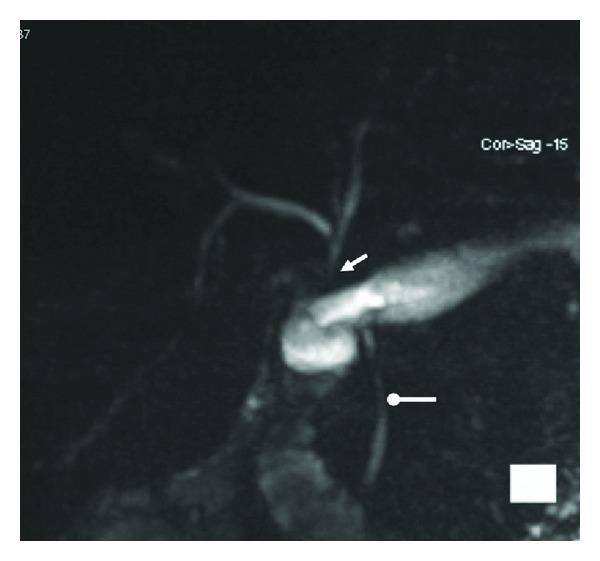

Introduction. Most surgeons prefer Roux-en-Y hepaticojejunostomy (RYHJ) for biliary reconstruction following a common bile duct (CBD) injury. However, in patients with a Roux-en-Y gastric bypass (RYGB) a RYHJ may be technically challenging and can interfere with bowel physiology induced by RYGB. The use of a hepaticoduodenostomy (HD) resolves both these issues. Presentation of Case. We present a case of CBD injury during laparoscopic cholecystectomy one year after laparoscopic RYGB for morbid obesity. Due to adhesions and previous surgery with RYGB, we did not want to interfere with the RYGB physiology by anastomosing the CBD to the jejunum or ileum. Succeeding a full Kocher's maneuver we performed biliary reconstruction by a tension-free end-to-side HD. The postoperative recovery was uneventful and the patient was discharged after eight days. At four-month follow-up, the patient had stable weight and normal laboratory test results. MRCP demonstrated normal intra- and extrahepatic bile ducts with status after HD. Discussion. We propose that HD should be considered in treatment of CBD injury in post-RYGB patients as it may reduce the risk of interfering with the post-RYGB physiology.

引言。大多数外科医生在胆总管(CBD)损伤后进行胆道重建时更倾向于采用 Roux-en-Y 肝空肠吻合术(RYHJ)。然而,对于接受 Roux-en-Y 胃旁路术(RYGB)的患者,RYHJ 在技术上可能具有挑战性,并且可能干扰由 RYGB 引起的肠道生理功能。肝十二指肠吻合术(HD)的应用解决了这两个问题。病例介绍。我们报告一例病态肥胖患者在腹腔镜 RYGB 术后一年行腹腔镜胆囊切除术时发生 CBD 损伤的病例。由于粘连以及既往的 RYGB 手术,我们不想通过将 CBD 与空肠或回肠吻合来干扰 RYGB 的生理功能。在完成充分的 Kocher 手法后,我们通过无张力端侧 HD 进行了胆道重建。术后恢复顺利,患者在八天后出院。在四个月的随访中,患者体重稳定,实验室检查结果正常。磁共振胰胆管造影(MRCP)显示肝内和肝外胆管正常,HD 术后情况良好。讨论。我们建议在治疗 RYGB 术后患者的 CBD 损伤时应考虑采用 HD,因为它可能降低干扰 RYGB 术后生理功能的风险。